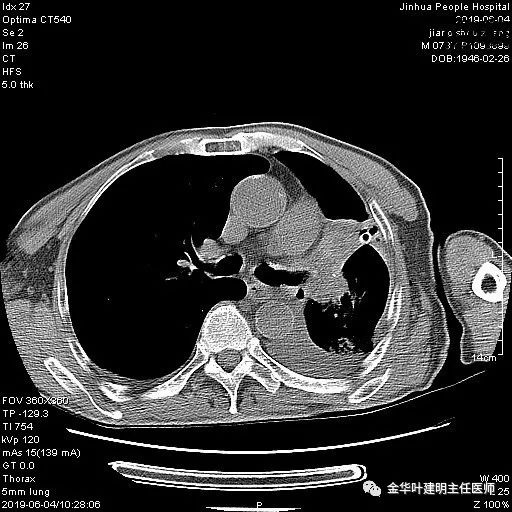

考虑左侧大量胸腔积液,遂进一步胸部CT检查:

以上是肺窗表现,下面为纵隔窗影像: